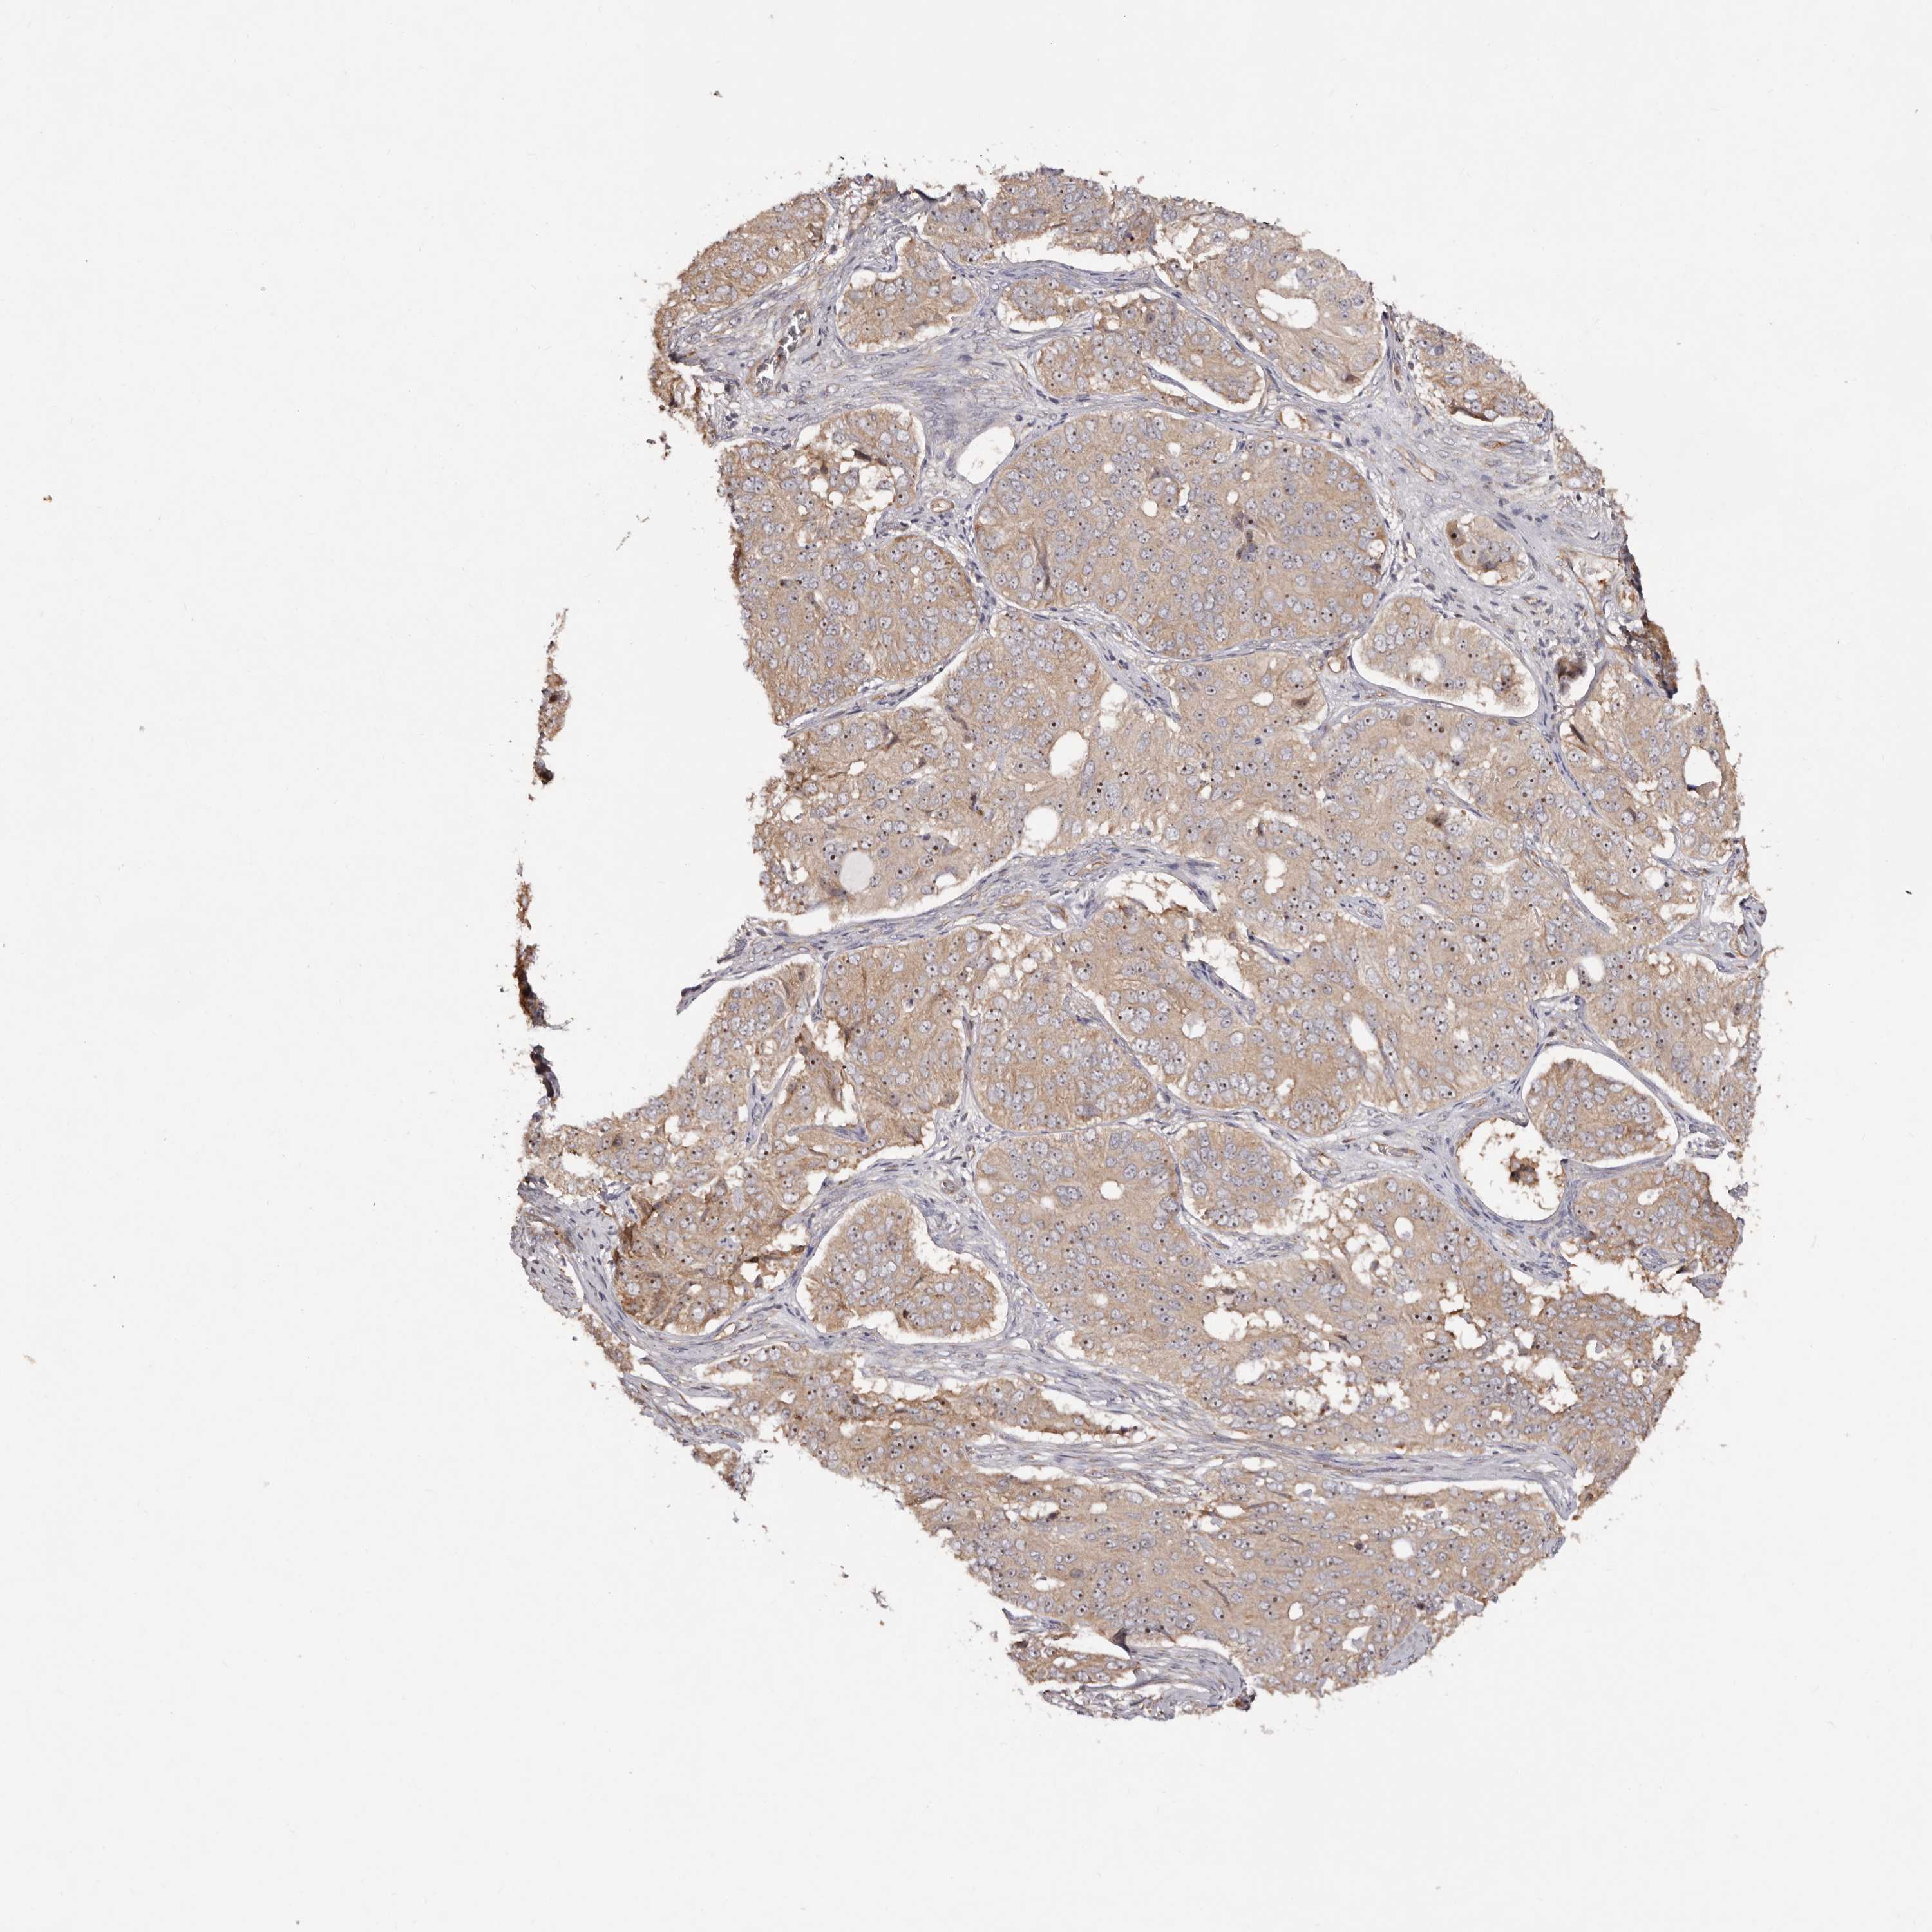

OVARIAN CANCER - Protein expressioni

A mouse-over function shows sample information and annotation data. Click on an image to view it in a full screen mode. Samples can be filtered based on level of antibody staining by selecting one or several of the following categories: high, medium, low and not detected. The assay and annotation is described here.

Note that samples used for immunohistochemistry by the Human Protein Atlas do not correspond to samples in the TCGA dataset.

Antibody stainingi

Antibody staining in the annotated cell types in the current human tissue is reported as not detected, low, medium, or high, based on conventional immunohistochemistry profiling in selected tissues. This score is based on the combination of the staining intensity and fraction of stained cells.

Each image is clickable and will lead to virtual microscopy that enables deeper exploration of all samples and also displays staining intensity scores, fraction scores and subcellular localization as well as patient and tissue information for each sample.

Antibody HPA031153

Antibody CAB004027

Cystadenocarcinoma, serous, NOS

Carcinoma, endometroid

Cystadenocarcinoma, mucinous, NOS

Carcinoma, NOS